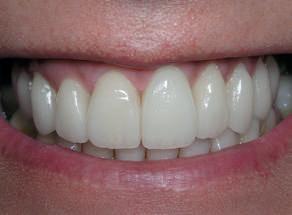

De assinalar que o desgaste do esmalte vestibular, proximal e incisal dos dentes preparados foi quase nulo e a preservação da vitalidade pulpar foi conseguida em todos os dentes (Fig. 3).

Decidiu-se descruzar a mordida e preencher os corredores vestibulares à custa de aderir umas facetas com um volume vestibular e um aumento do comprimento dos dentes bastante considerável (Fig. 4).

Figura 3